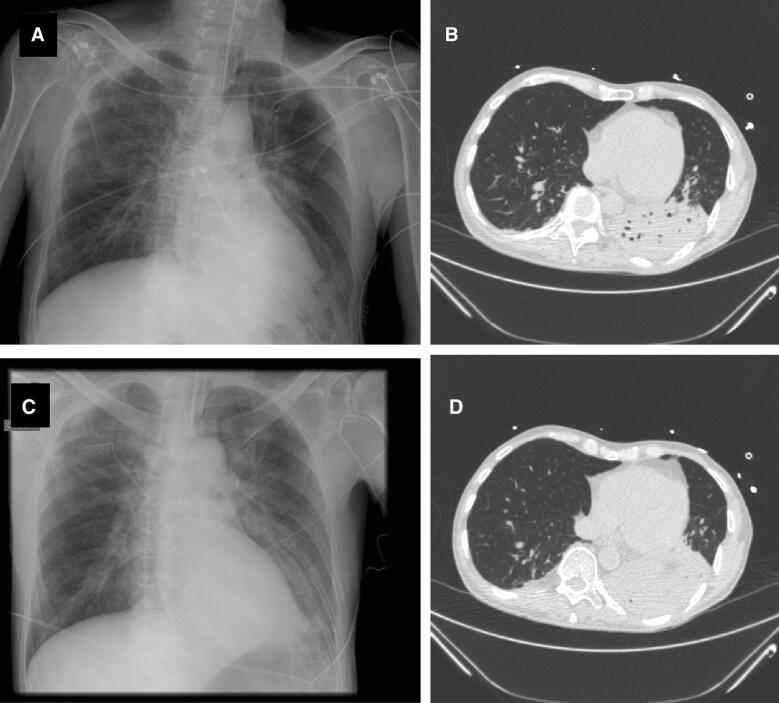

Ventilator-associated pneumonia (VAP) is one of the most frequent ICU-acquired infections. Reported incidences vary widely from 5 to 40% depending on the setting and diagnostic criteria. VAP is associated with prolonged duration of mechanical ventilation and ICU stay. The estimated attributable mortality of VAP is around 10%, with higher mortality rates in surgical ICU patients and in patients with mid-range severity scores at admission. Microbiological confirmation of infection is strongly encouraged. Which sampling method to use is still a matter of controversy. Emerging microbiological tools will likely modify our routine approach to diagnosing and treating VAP in the next future. Prevention of VAP is based on minimizing the exposure to mechanical ventilation and encouraging early liberation. Bundles that combine multiple prevention strategies may improve outcomes, but large randomized trials are needed to confirm this. Treatment should be limited to 7 days in the vast majority of the cases. Patients should be reassessed daily to confirm ongoing suspicion of disease, antibiotics should be narrowed as soon as antibiotic susceptibility results are available, and clinicians should consider stopping antibiotics if cultures are negative.

呼吸机相关性肺炎(VAP)是重症监护病房(ICU)获得性感染中最常见的一种。根据不同的环境和诊断标准,其发病率差异很大,从 5%到 40%不等。VAP 与机械通气时间和 ICU 住院时间延长有关。VAP 的估计归因死亡率约为 10%,外科 ICU 患者和入院时中度严重程度评分的患者死亡率更高。强烈鼓励对感染进行微生物学确认。使用哪种采样方法仍然存在争议。新出现的微生物学工具可能会在未来改变我们对 VAP 的诊断和治疗的常规方法。VAP 的预防基于尽量减少机械通气的暴露并鼓励尽早脱离机械通气。结合多种预防策略的综合方案可能会改善结果,但需要进行大规模的随机试验来证实这一点。在大多数情况下,治疗应限制在 7 天以内。应每天重新评估患者以确认持续存在疾病的怀疑,一旦获得抗生素敏感性结果,就应尽快缩小抗生素范围,如果培养结果为阴性,临床医生应考虑停止使用抗生素。